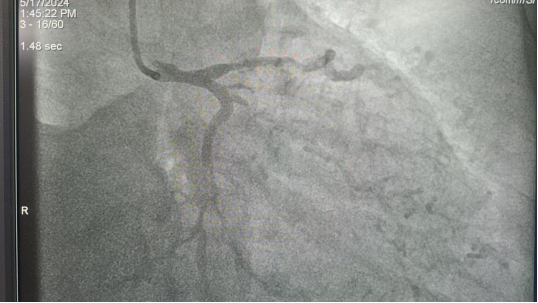

该心电图源自山泉镇公立卫生院的一位50岁男性患者,该患者表现为胸痛、头晕、畏寒、呕吐、血压高,当地医院李昌贵医生为患者行心电图检查发现异常后,当即在群中邀请我院远程会诊。

我院心内科副主任罗阳查看信息后,立即明确指出:患者所患疾病考虑为高危左主干心梗,此类病情具有极高的死亡风险。罗主任强烈建议,在取得患者家属同意的前提下,应尽快将其转诊至我院进行急诊手术。